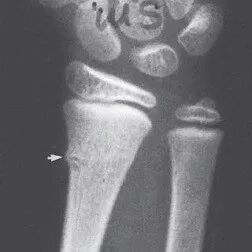

Finally, there are epiphyseal injuries. These refer to injuries to a bone structure unique to children: their growth plates.

(Editor's note: Growth plates are the areas of growing tissue at the ends of long bones of children and adolescents. When kids finish growing, their growth plates become deactivated and turn to bone. Because of the role of growth plates in a child’s vertical growth, parents may worry about keeping their child’s growth plates healthy. Other than growth plates, genes, nutrition, and exercise also help determine how tall your child will grow.)